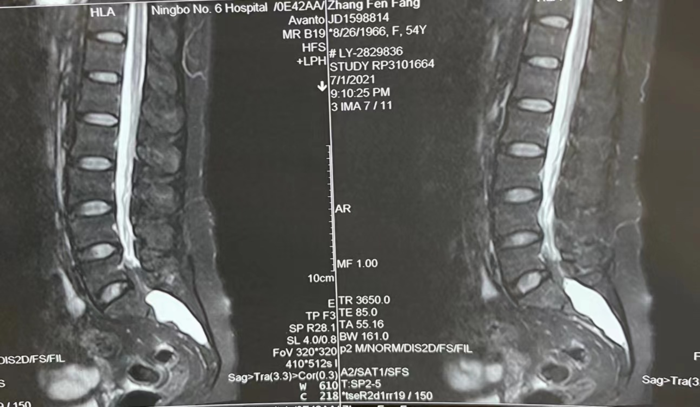

患者术前腰骶椎核磁共振(如下图示)显示大型骶管囊肿(S1-3,NaborsIIB型)